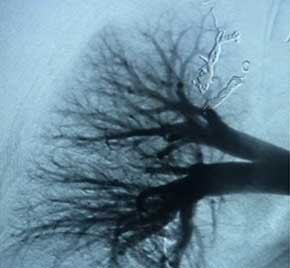

Hemoptysis treated with Embold Fibered​ Coils

Scan of vein before placement of coil. Visualizing the pulmonary artery​

Scan of vein after Embold fibered coil. After Embold Fibered placement​

Keshav Anand, MD

University of Utah

Salt Lake City, UT